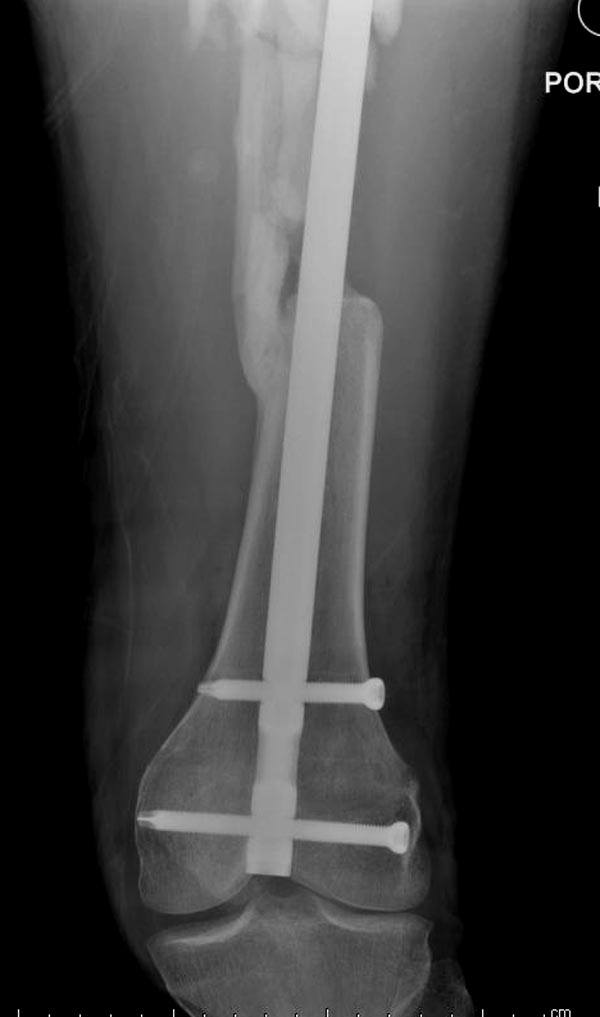

Здесь выставлен ренгенограммы больного, ему 21, травму получил в

результате высокоскоростной погони на украденной машине, которая

закончилась смертью трех остальных“боевых комрадов”. Начатую коллегой

открытую операцию на шейке пришлось закончить мне, установкой винтов и

ретроградной фиксацией бедра. Выписка в обычное сроки и наблюдался

амбулаторно. Каждый раз напоминали о возможности осложнений ввиде

несращения! По истечению 4 месяцев появились признаки варусной

деформации. На СТ срезах несращение шейки и бедра. Риминг, замена на

более толстый гвоздь и вальгусная остеотомия.